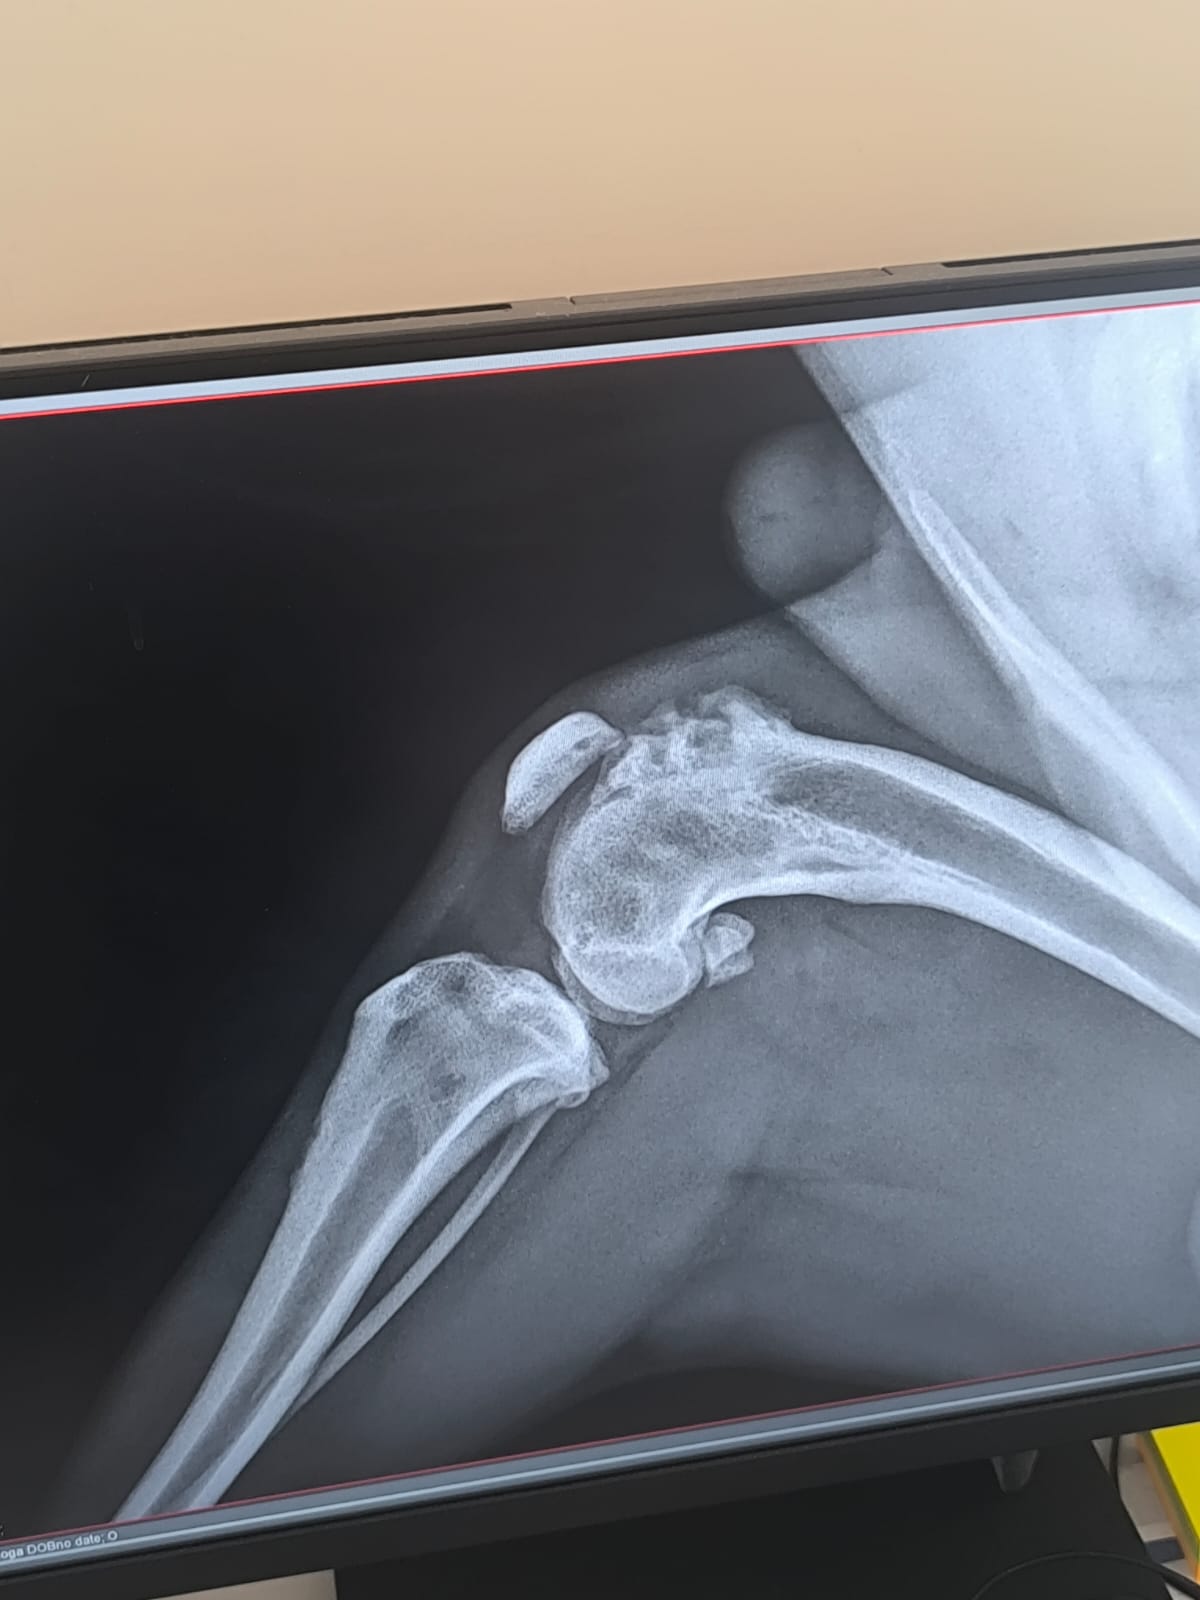

Im September 2025 haben wir Ihnen die kleine Finija vorgestellt: Gerade einmal vier Monate alt, wurde sie in einem erschütternden Zustand gefunden. Beide Hinterbeine waren gebrochen, eine Fortbewegung war für sie nur noch auf den Vorderpfoten möglich. Trotz starker Schmerzen zeigte Finija eine unglaubliche Willenskraft – ein kurzes Video aus…